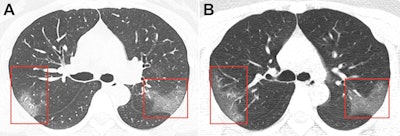

Unenhanced chest CT scans of the patient showed multiple peripheral ground-glass opacities in both of her lungs, and subsequent DNA tests were positive for 2019-nCoV. CT scans acquired three days after treatment revealed progressive pulmonary opacities, indicating that the patient's condition was worsening despite treatment.

CT scan of a 33-year-old woman infected with the novel coronavirus shows multiple bilateral ground-glass opacities evident on the initial scan (A) and progressive ground-glass opacities, without subpleural sparing, on a scan obtained three days later (B). Image courtesy of the RSNA.Chest images, in conjunction with epidemiologic characteristics and laboratory tests, were critical in diagnosing coronavirus-infected pneumonia in this patient and also monitoring disease progression, Lei and colleagues noted.

"Imaging exams are a key component in diagnosing 2019-nCoV," the RSNA said in a statement. "Early disease recognition is critical not only for prompt treatment but also for patient isolation and effective public health containment and response."